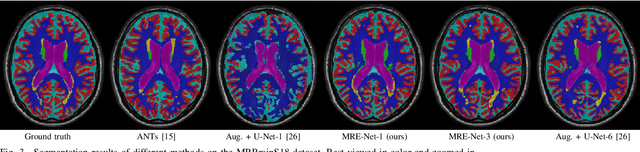

Abstract:Medical image segmentation has achieved remarkable advancements using deep neural networks (DNNs). However, DNNs often need big amounts of data and annotations for training, both of which can be difficult and costly to obtain. In this work, we propose a unified framework for generalized low-shot (one- and few-shot) medical image segmentation based on distance metric learning (DML). Unlike most existing methods which only deal with the lack of annotations while assuming abundance of data, our framework works with extreme scarcity of both, which is ideal for rare diseases. Via DML, the framework learns a multimodal mixture representation for each category, and performs dense predictions based on cosine distances between the pixels' deep embeddings and the category representations. The multimodal representations effectively utilize the inter-subject similarities and intraclass variations to overcome overfitting due to extremely limited data. In addition, we propose adaptive mixing coefficients for the multimodal mixture distributions to adaptively emphasize the modes better suited to the current input. The representations are implicitly embedded as weights of the fc layer, such that the cosine distances can be computed efficiently via forward propagation. In our experiments on brain MRI and abdominal CT datasets, the proposed framework achieves superior performances for low-shot segmentation towards standard DNN-based (3D U-Net) and classical registration-based (ANTs) methods, e.g., achieving mean Dice coefficients of 81%/69% for brain tissue/abdominal multiorgan segmentation using a single training sample, as compared to 52%/31% and 72%/35% by the U-Net and ANTs, respectively.